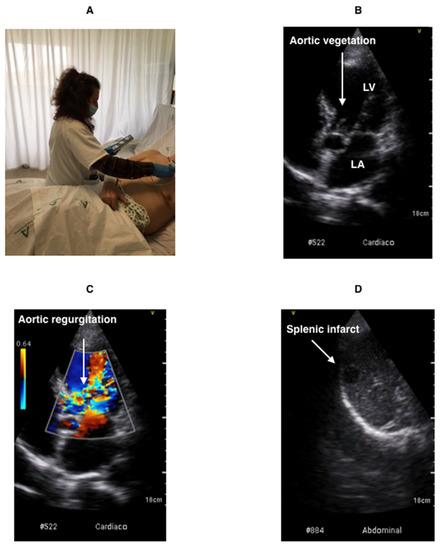

The POCUS examination was performed using the Vscan Extend dual ultrasound system (General Electric). Its dimensions are 168 × 76 × 22 mm and its weight is 321 g. It has a sectorial and linear probe, B-mode and Doppler Color. In this study, sectorial probe was used. It has broad bandwidth phased array (1.7–3.8 MHz), field of view for black and white imaging (up to 70 degrees with maximum depth of 24 cm) and color flow sector representing blood flow within an angle of up 40 degrees. With the greater penetration of lower ultrasound frequencies, high-quality harmonic imaging at greater depth can be performed. All images were recorded on a micro-SD memory card and transferred to the computer for review and more complex measurements (Figure 1).

Table 6 shows the usefulness of POCUS for the detection of hepatomegaly, splenomegaly and septic embolisms, which are all common findings in IE (Figure 1). For this purpose, we analyzed a sample of 186 patients (72.1%) who underwent an abdominal imaging test (ultrasound, CT). Using this as a reference method, the usefulness of POCUS for the detection of hepatomegaly and splenomegaly presented sensitivity values of 92% and 92%, respectively, and specificity values of 96% and 98%, respectively. Septic embolisms were observed in seven patients (9.6%). However, the sensitivity in detecting hepatic and splenic infarction (Video S3) was only 60% and 50%, respectively. It was not possible to properly assess the values for renal infarctions due to insufficient data.

The following supporting information can be downloaded at: https://www.mdpi.com/article/10.3390/jcm11133636/s1, Video S1 (vegetation on aortic valve). Video S2 (aortic regurgitation). Video S3 (splenic infarct).

Figure 1. Demonstration of the POCUS technique. (A). POCUS at the patient’s hospital bedside. (B). Vegetation on aortic valve. (C). Severe aortic regurgitation. (D). Splenic infarction. LA: left atrium. LV: left ventricle.